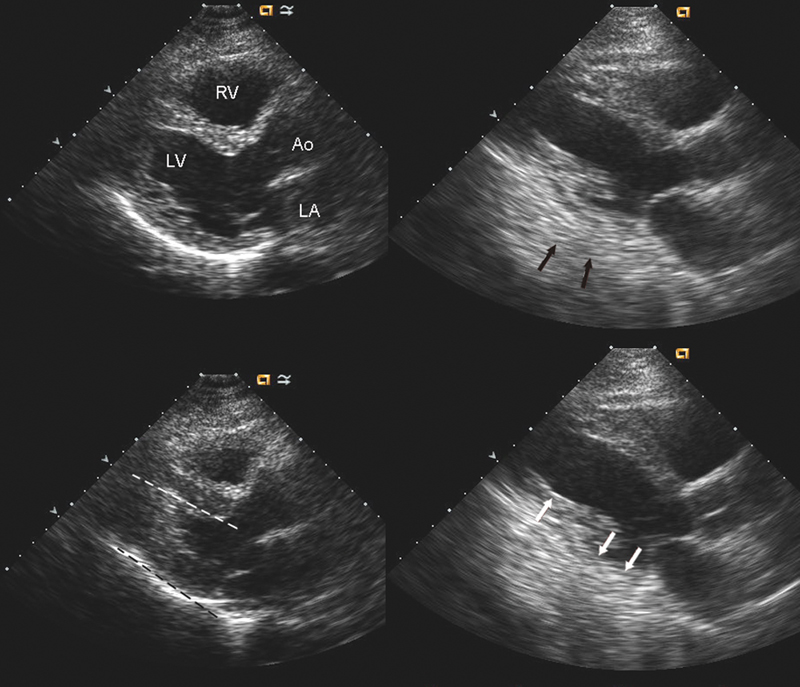

فحوصات تشخيصية لبعض امراض القلب والشرايين التاجية